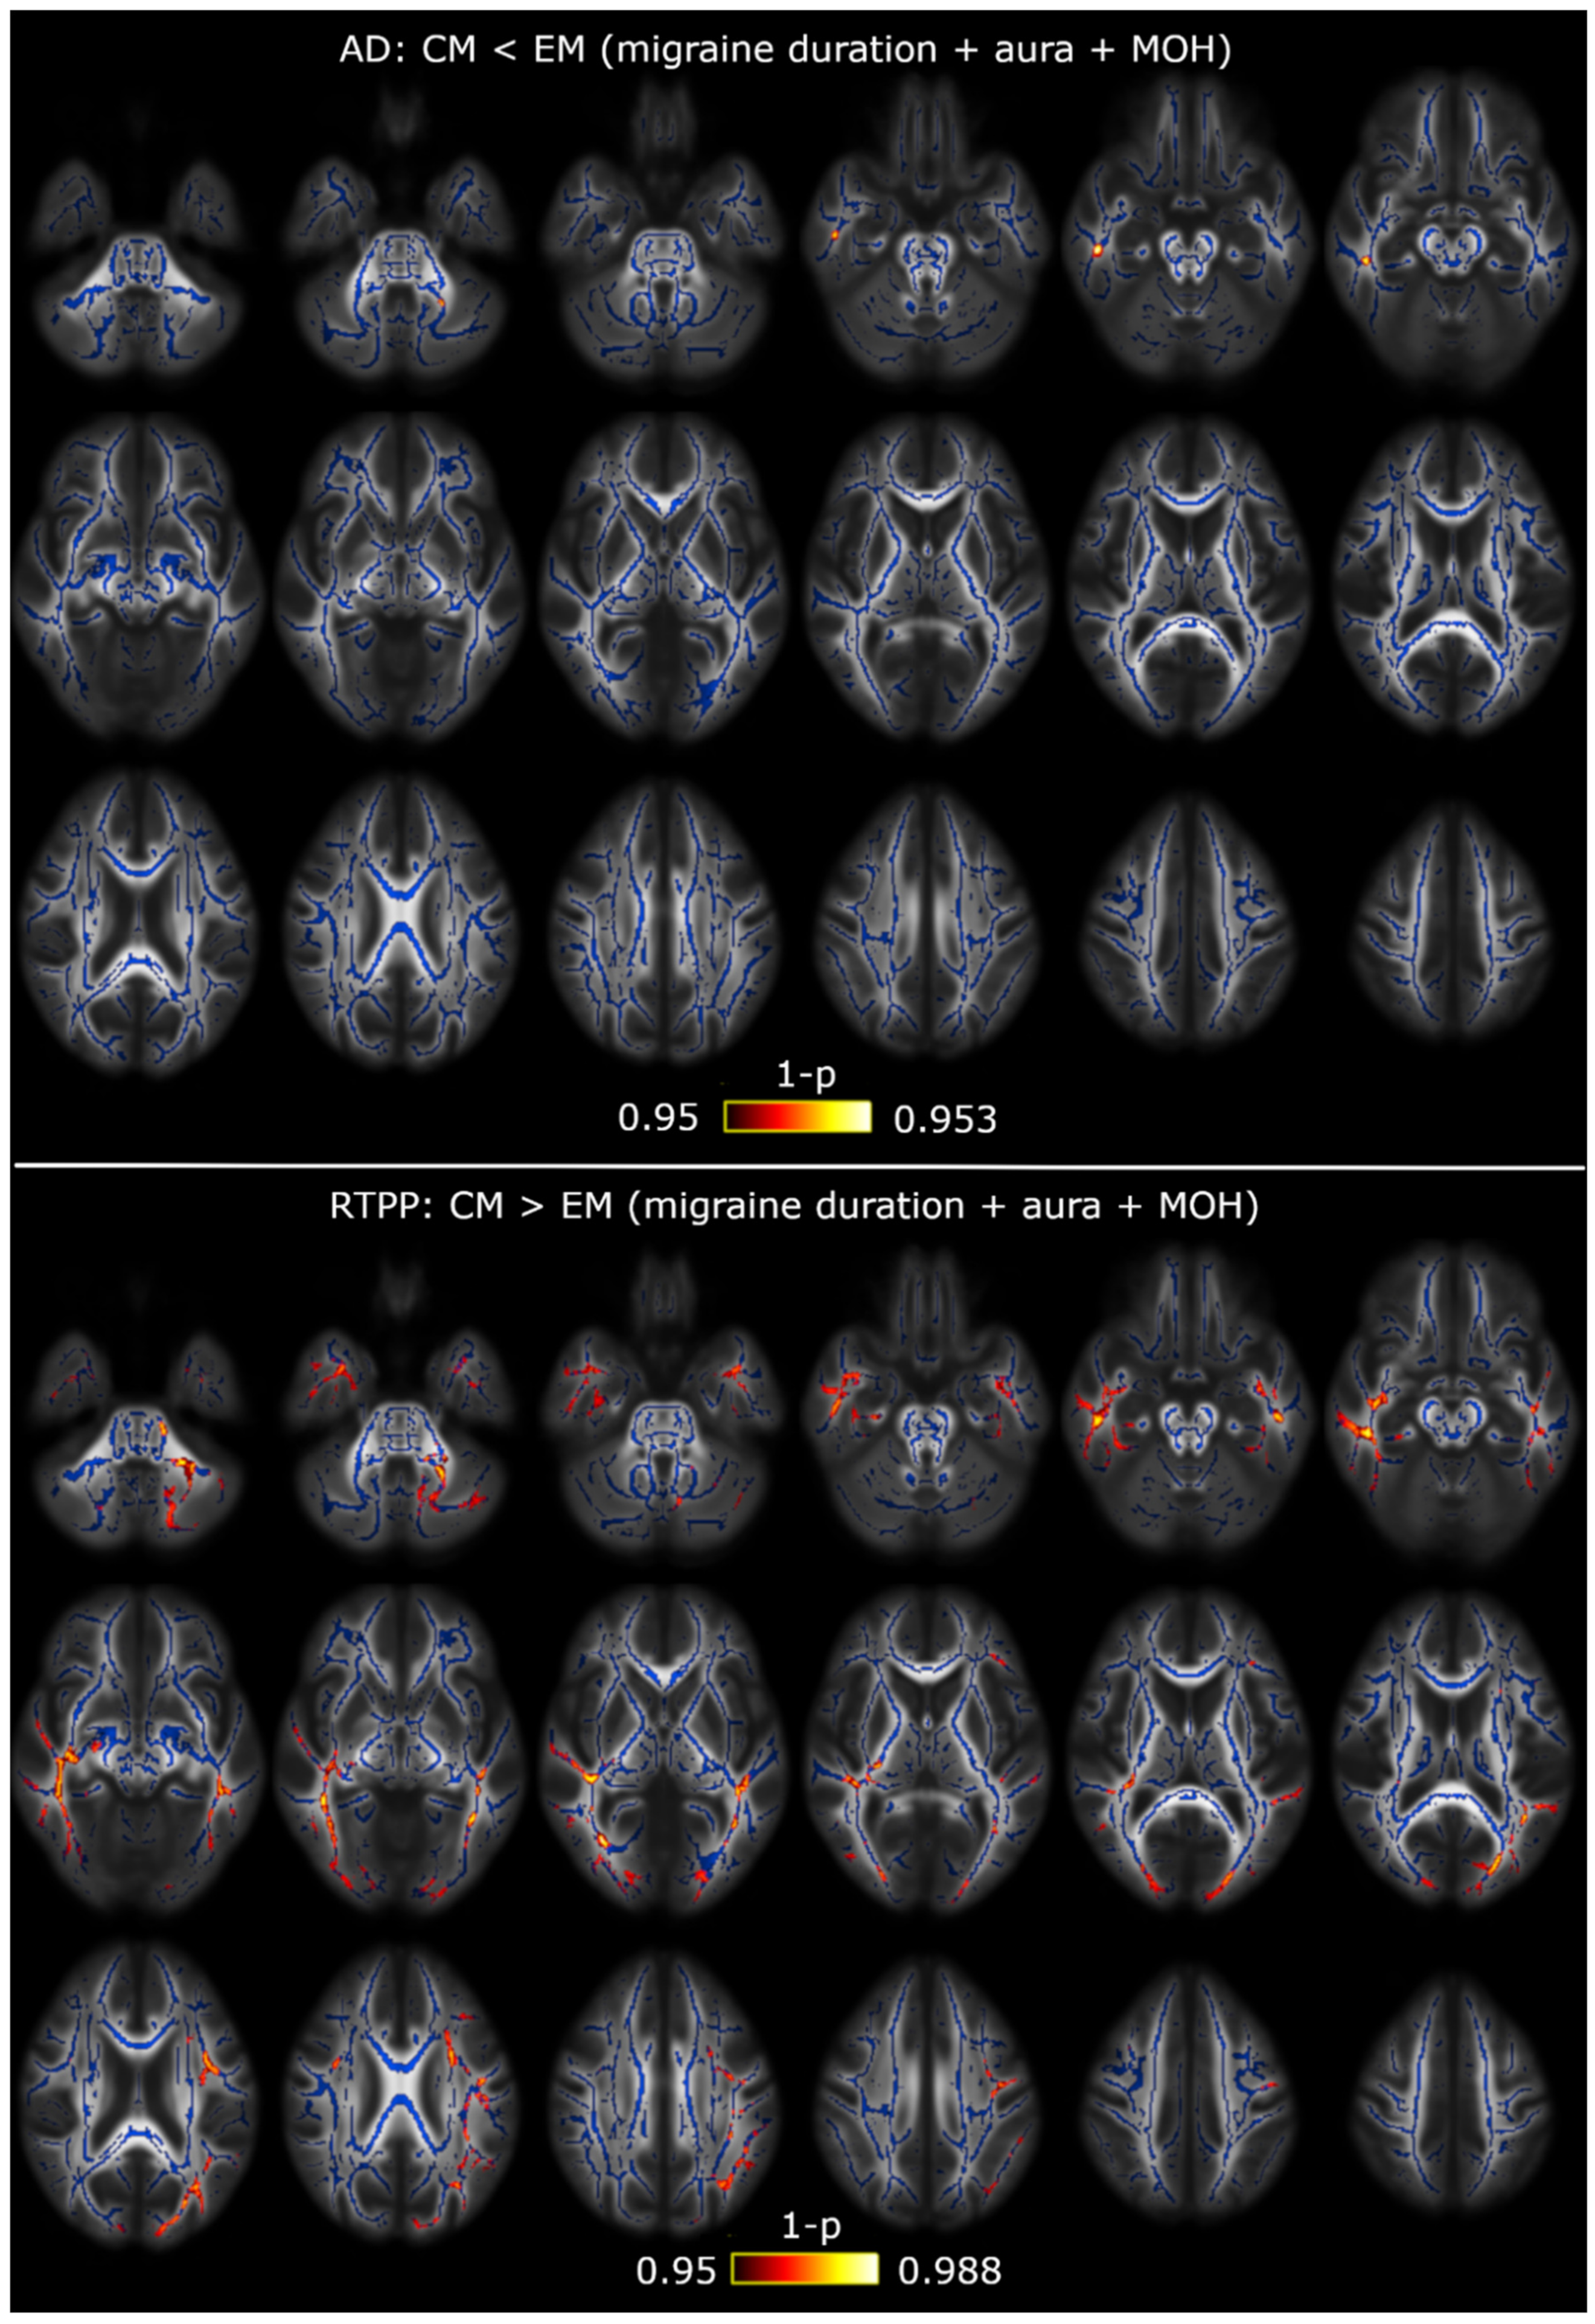

3.1. TBSS

3.2. TBSS with Covariates